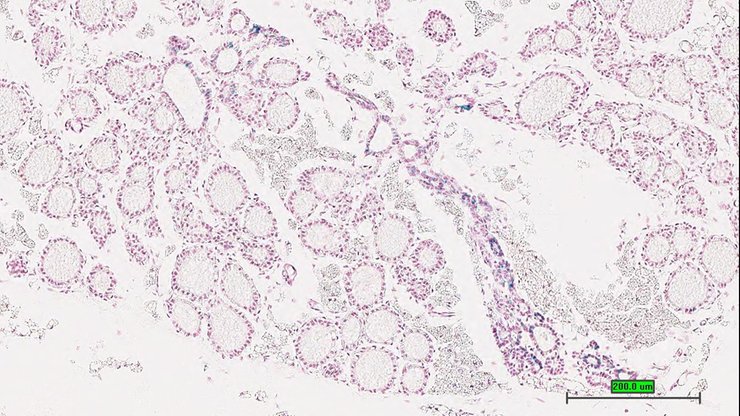

TS28: testis Present UC Davis_1870227

Specimen UC Davis_1870228: postnatal adult; Adamts9tm1b(KOMP)Wtsi/Adamts9+ (more )

Structure Level Pattern Image Note

TS28: epididymis Present UC Davis_1870228